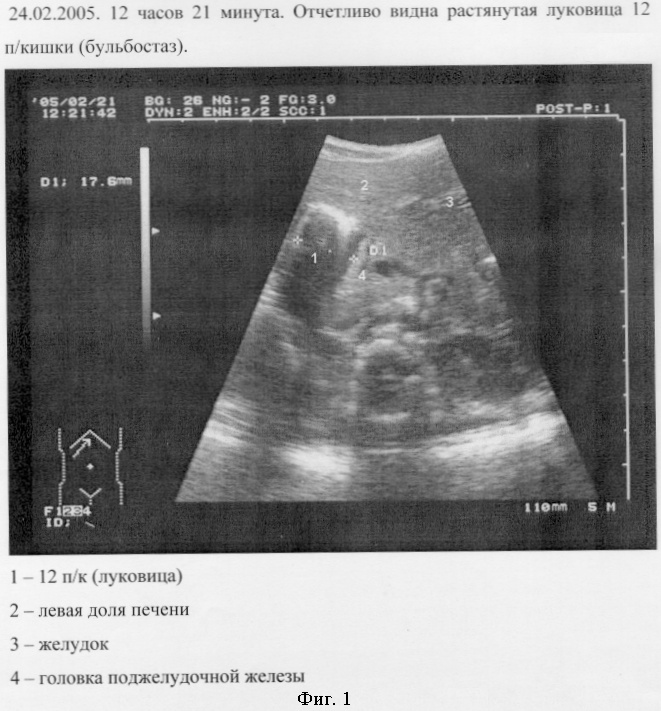

На пятые сутки раннего послеоперационного периода, при возвышенном положении больного, составившего 20°, после обзорной УЗИ-графии органов брюшной полости, ультразвуковой датчик установлен в эпигастральной области (фиг. 1).

24.02.2005. 12 часов 21 минута. Отчетливо видна растянутая луковица 12 п/кишки (бульбостаз).